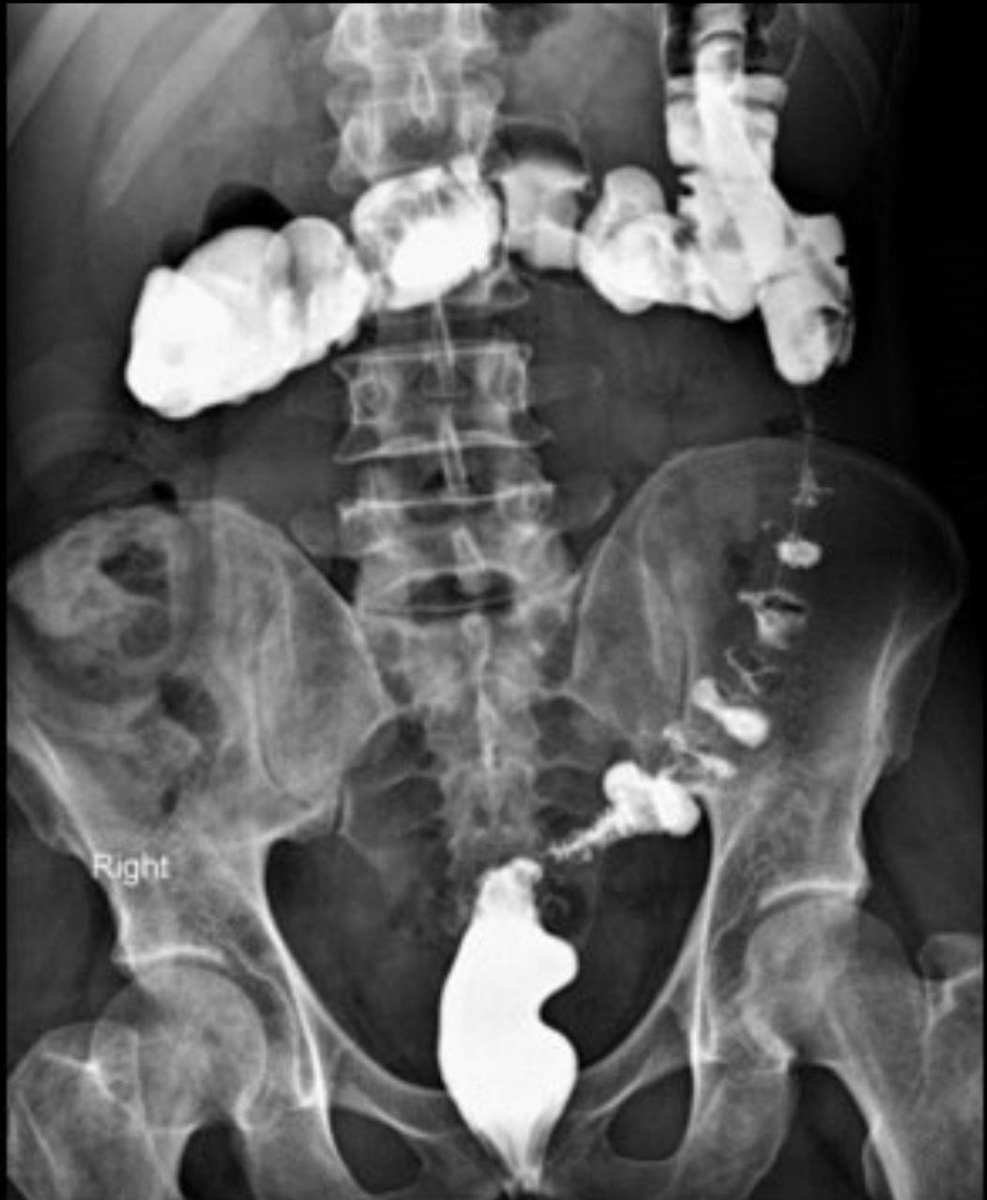

При ирригоскопии проводяи исследование толстой кишки с ретроградным введением в нее рентгенконтрастного препарата (посредством клизмы).

На сегодняшний день ирригоскопию проводят чаще всего для выявления пороков развития толстой кишки (до сих пор проводится у детей), для оценки ее функциональных особенностей, также данный метод позволяет выявлять опухоли толстой кишки.